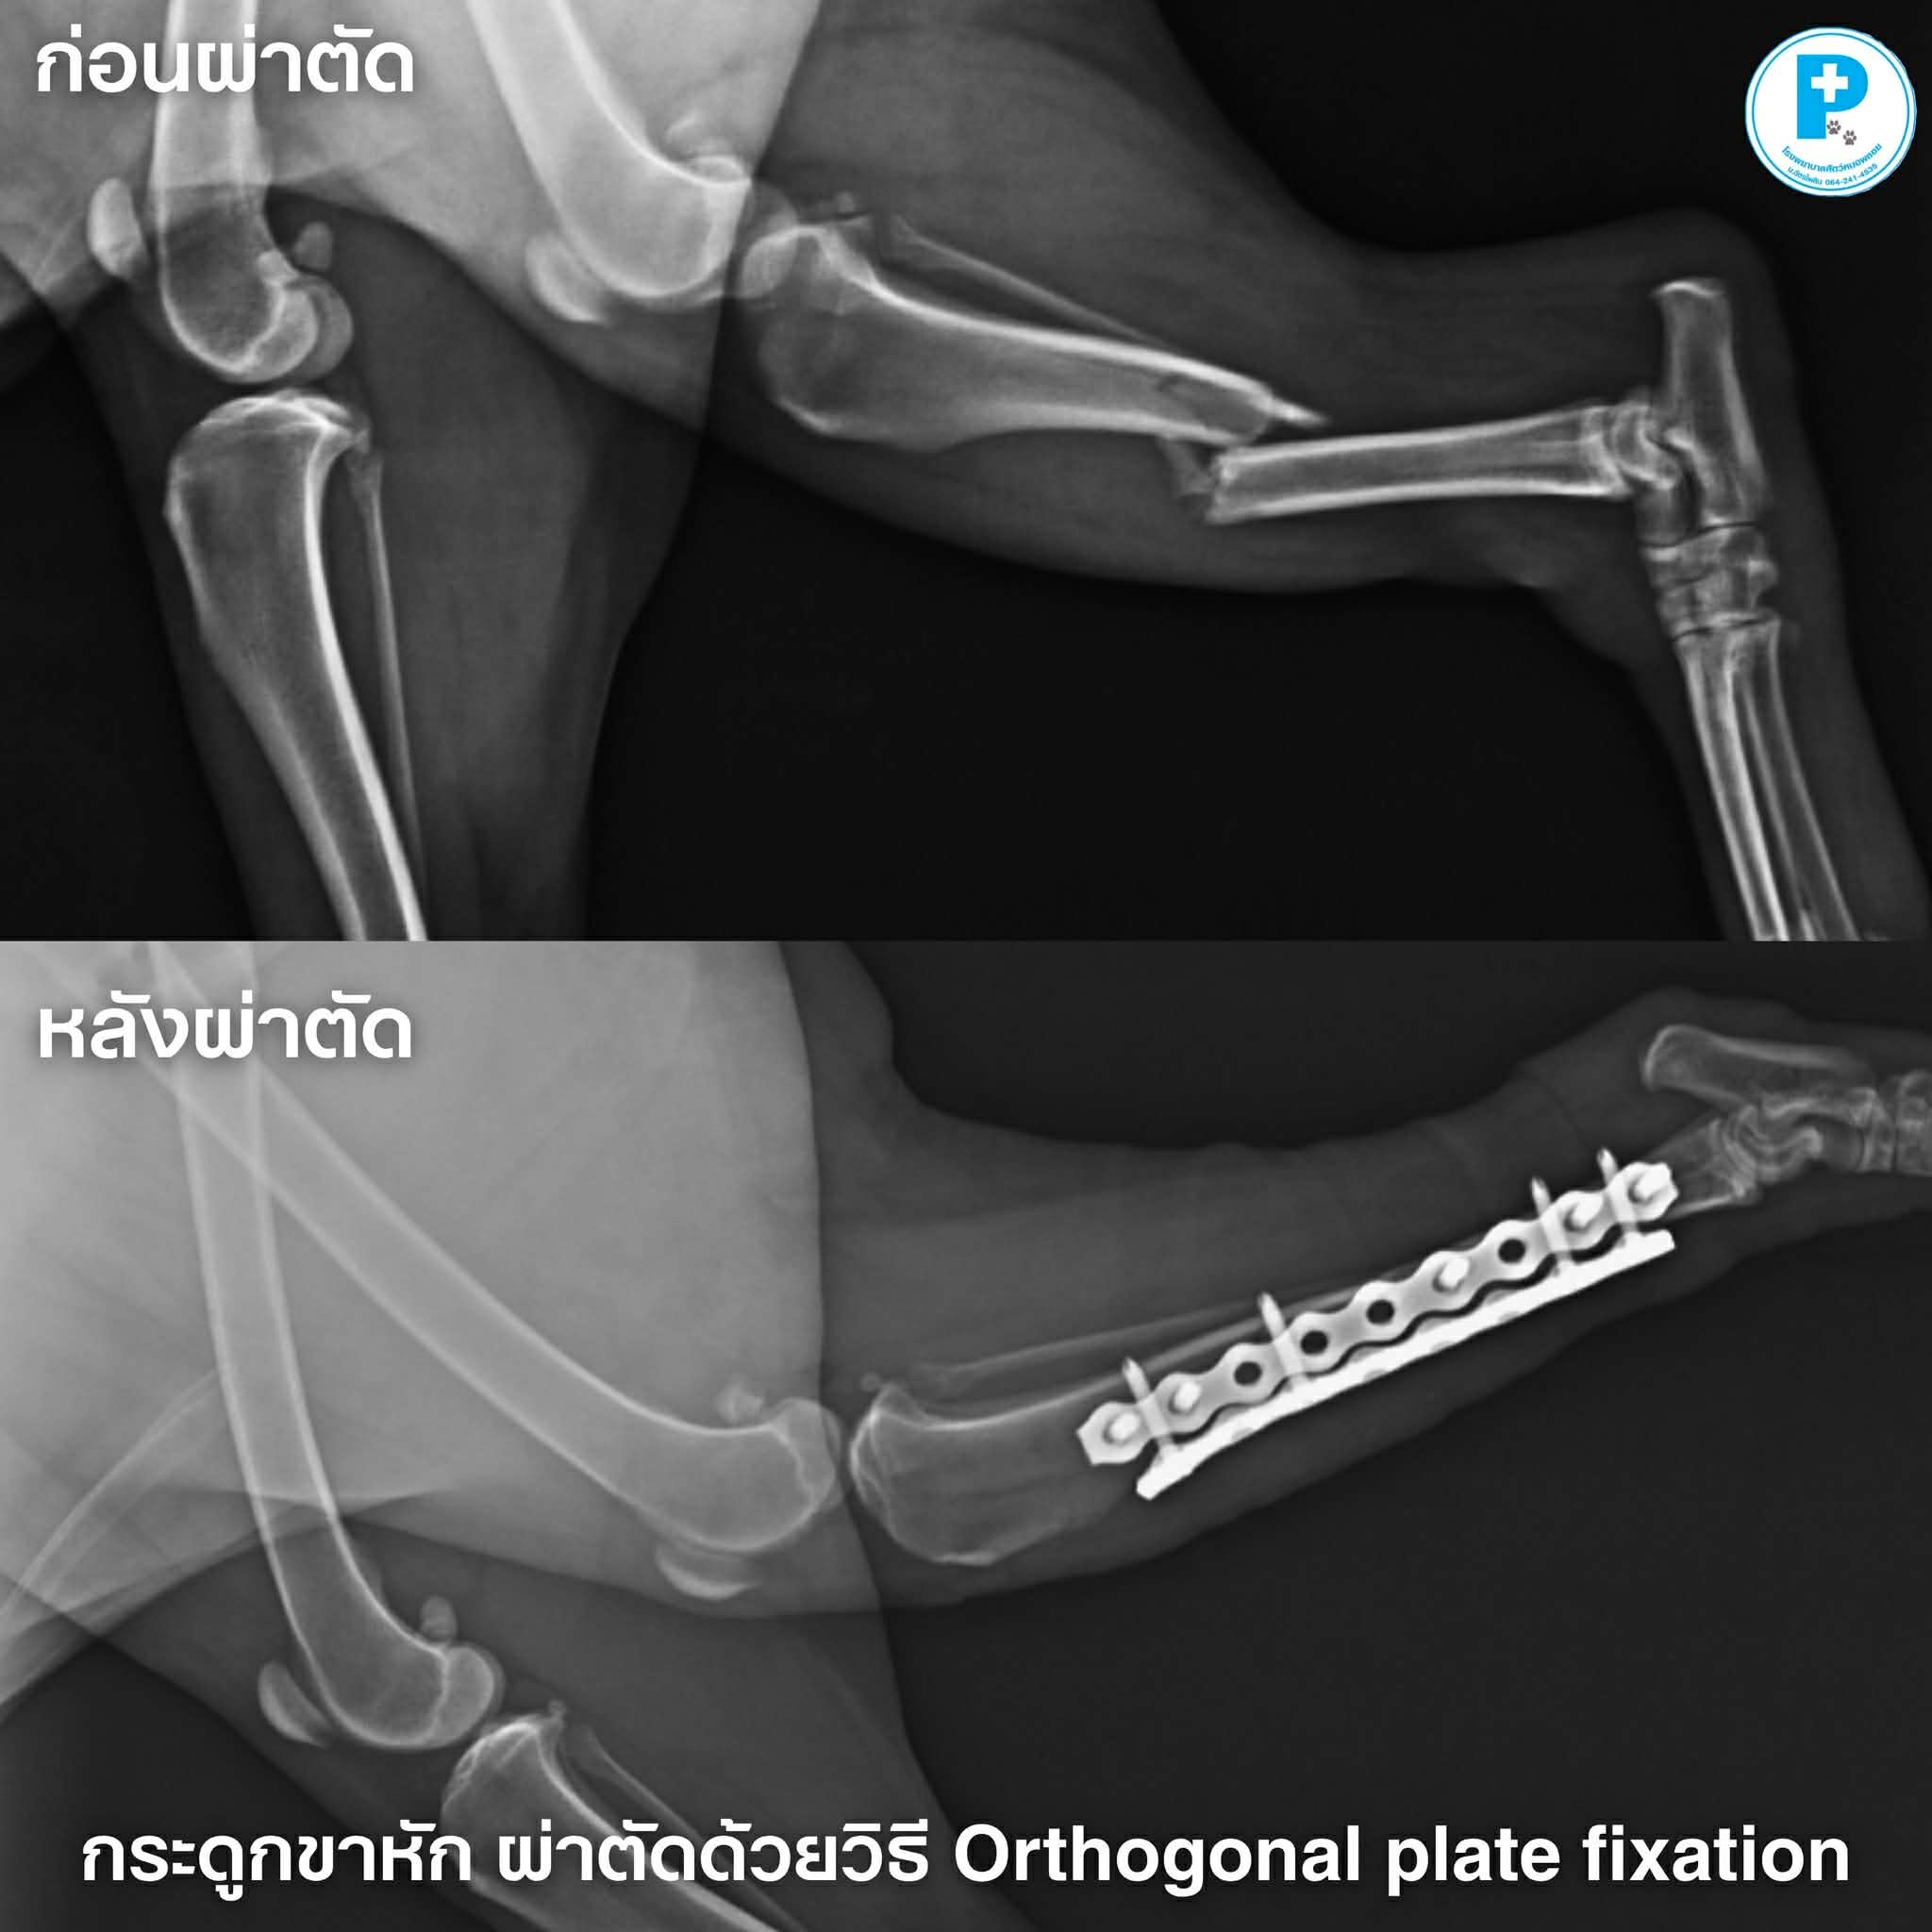

กระดูกหน้าแข้งซ้ายหักแบบเฉียง (Complete left tibial oblique fracture)

ผ่าตัดดามกระดูกด้วยเทคนิค Orthogonal plate fixation เพื่อเพิ่มความแข็งแรง รองรับน้ำหนักตัวที่ค่อนข้างมาก

ภาพก่อน–หลังผ่าตัด จะเห็นการจัดแนวกระดูกที่ดีขึ้น และมีการยึดตรึงด้วย plate อย่างเหมาะสม